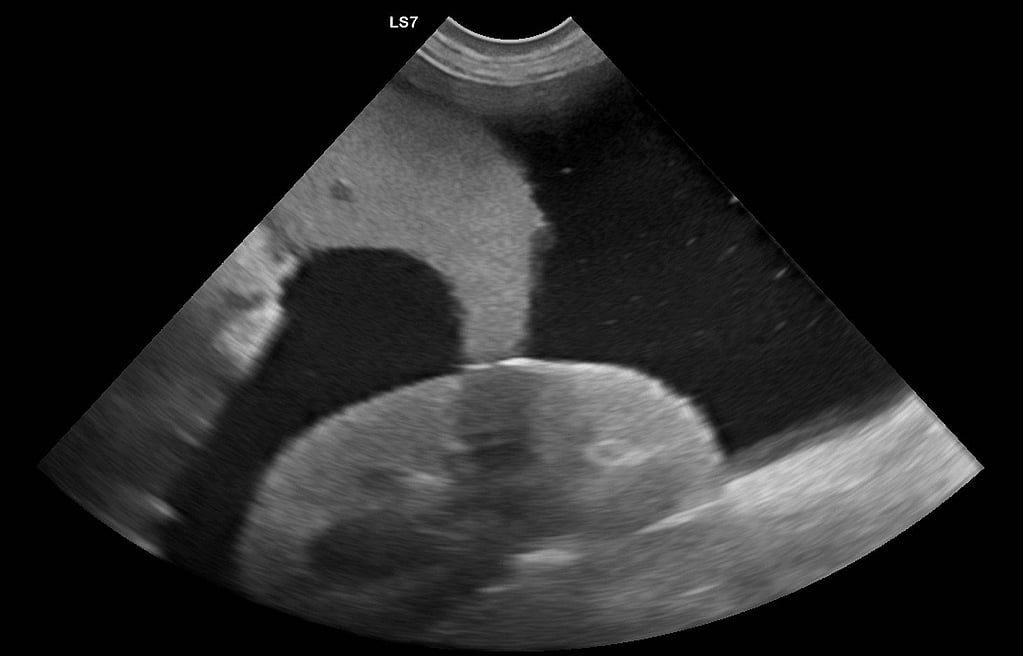

Abdominal POCUS

Durchführung im Stehen, Sitzen oder Liegen (so wie der Patient es toleriert), Einüben des POCUS-Protokolls, Darstellung aller "5 locations" mit Befunderhebung und Interpretation.